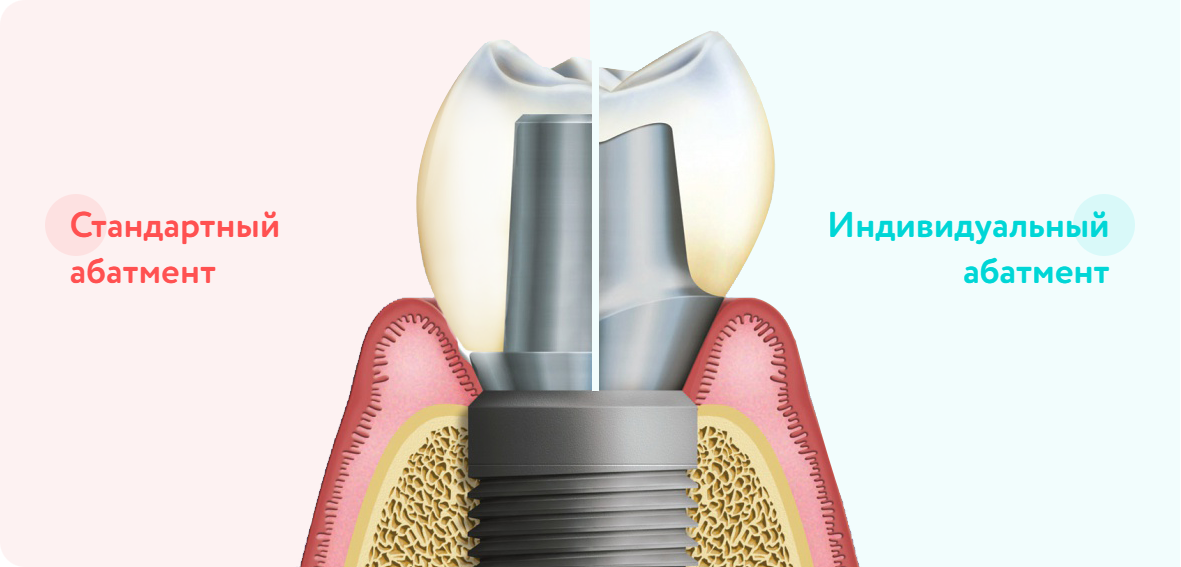

Используем только индивидуальные абатменты при протезировании.

Абатмент — это деталь, которая вкручивается в имплант и на которую крепится коронка.

Именно от абатментов зависит надежность и долговечность всей конструкции.

В некоторых клиниках, с целью экономии, могут практиковать установку стандартных абатментов — которые НЕ учитывают индивидуальную анатомию пациента, это приводит к снижению срока службы конструкции и при этом страдает эстетика.

Стандартная форма абатмента и размеры не могут повторить форму зуба. Из-за чего увеличивается риск того, что элементы системы будут установлены некачественно и конструкция прослужит ограниченное время.

Изготовление и крепление постоянного абатмента

Шаблонный накостный элемент конструкции меняется на индивидуальный. Обеспечивает более надежное соединение с коронкой.